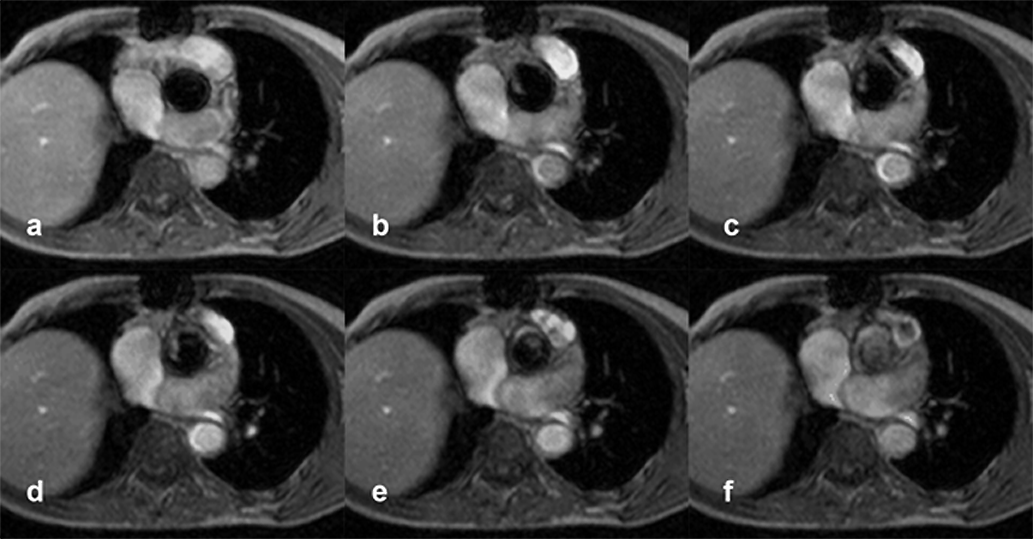

Figura 14-25:

Patient with several transient ischemic at­tacks. Gradient-echo images four mil­li­me­ters above the aor­tic valve during different phases of the cardiac cycle show a pen­du­lat­ing thrombus.

These studies must have reasonable temporal resolution to describe the dif­fe­rent pha­ses of the heart cycle, typically 16 or more, depending on the clinical question (Figure 14-25). The results will yield an image with muscular tissue in gray, static li­quid in white and high-velocity jets in black (signal void). Con­se­quent­ly, both or­di­na­ry flow and regurgitant jets are seen, but cannot be quan­ti­fied immediately. One quan­ti­fi­ca­tion method being employed is to measure the area (or volume) of the re­gur­gi­tant jet (signal void) and compare it to the area (or volume) of the chamber.